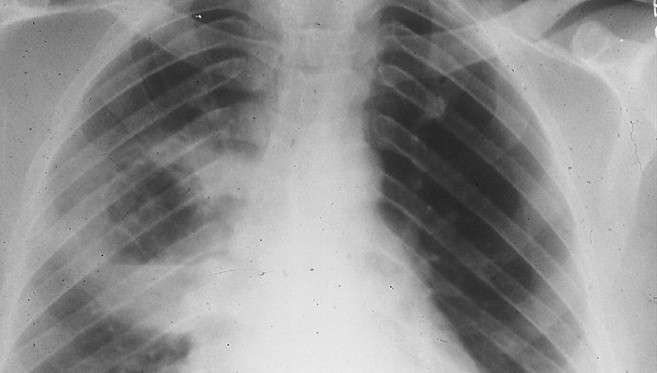

silicosis

El diputado del BNG plantea una moción en el Congreso solicitando cambios legislativos para el reconocimiento de incapacidad permanente en trabajadores del sector de la piedra afectados por silicosis

¿Qué incidencia tiene la silicosis, la enfermedad que ha llevado a los juzgados al presidente del Grupo Cosentino?